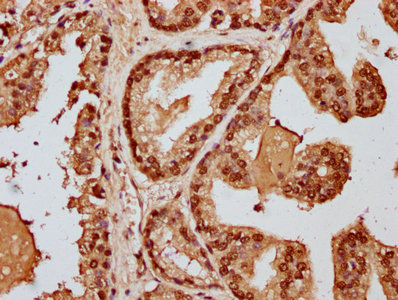

IHC image of CSB-PA010418OA128nme1HU diluted at 1:20 and staining in paraffin-embedded human prostate cancer performed on a Leica BondTM system. After dewaxing and hydration, antigen retrieval was mediated by high pressure in a citrate buffer (pH 6.0). Section was blocked with 10% normal goat serum 30min at RT. Then primary antibody (1% BSA) was incubated at 4°C overnight. The primary is detected by a biotinylated secondary antibody and visualized using an HRP conjugated SP system.